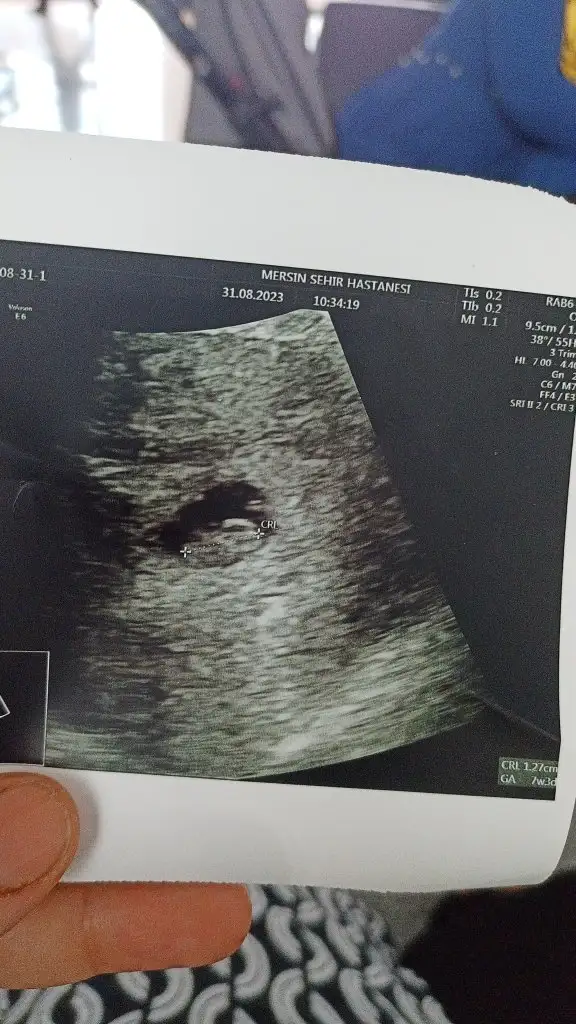

Ramzi teorisi okudum yüzde 97 dogruymuş.Ama neye göre bakcam ultrasona bilemedim. Size sormak istedim Bebeğim sağa daha yakın sanki bası da solda ayakları sağa bakıyor yani. Anlamadım ben. Sağlıklı olsun tabi kız erkek fark etmez ama merak ettim. İlk foto 5+5 iken 2.foto 9+3ken

Baya oldu girmeyeli. Şuan güncelliyorum ancaMerak eden varsa Bi KIZIMIZ Olacak inşallah Allah kısmet ederse zaten hissediyodum. Hatta testi yapmadan önce de pembe tulumlar aldıgım rüyalar görmüştüm. Saglıklı olsun da farketmez. Allah isteyen herkese versin inşallah. Duam sizinle, siz de duanızı eksik etmeyin lütfen